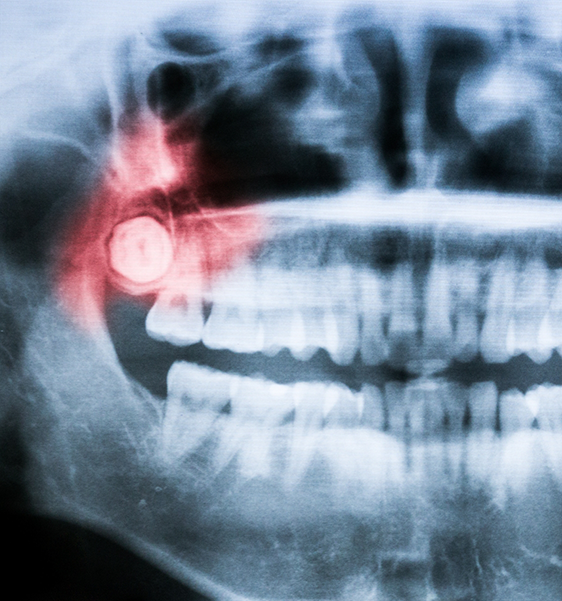

Wisdom teeth, also referred to as third molars, are the very last teeth to erupt through your gumline, typically between the ages of 16 and 24. While some people may only have one or two wisdom teeth, others can have all four or none at all. It’s important to note that not every wisdom tooth needs to be extracted. Dr. Mazhari can help determine whether allowing yours to grow in would compromise your oral health down the line by putting you at risk of developing a cyst, infection, or other complications. Call us today if you’re experiencing any pain or pressure in the back of your mouth that could be due to the need for wisdom tooth extraction in Alexandria.

Your wisdom tooth extraction procedure can vary based on whether your third molars are impacted below the gumline or if they have fully erupted. For impacted teeth, we may refer you next door to the expert oral surgeon that we collaborate with to offer our patients outstanding results and truly professional care. This would involve the surgical removal of the wisdom teeth by creating a window in the gumline and removing them.